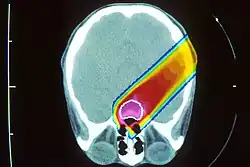

_and_IMRT_(left).jpg)

Рандомизованные исследования эффективности протонной терапии продолжаются до сих пор для разных видов рака[30] и показывают снижение частоты и последствий побочных эффектов сравнительно с другими видами лучевой терапии. Авторы из Стэнфордского университета опубликовали в 2020 году результаты исследования, выполненного на свыше чем 450 тысячах пациентов, из которых 5867 получили лечение протонным пучком[31]. Исследование показало трёхкратное снижение риска появления вторичных новообразований по всем видам рака, и 5-кратное для рака предстательной железы.

Главным преимуществом протонной терапии перед фотонной радиотерапией с модуляцией интенсивности (IMRT) является снижение побочных доз, получаемых здоровыми тканями, в особенности позади пика Брэгга. Таким образом, протонная терапия применяется чаще всего в случаях, когда опухоль расположена в тесном окружении жизнено важных органов (organs at risk — OAR): опухоли мозга, шеи, основания черепа. Также, предпочтение протонам часто отдаётся в случае лечения заболеваний у детей[32], поскольку большая ожидаемая продолжительность жизни и активно делящиеся клетки растущего организма требуют снижения побочных доз облучения[33].